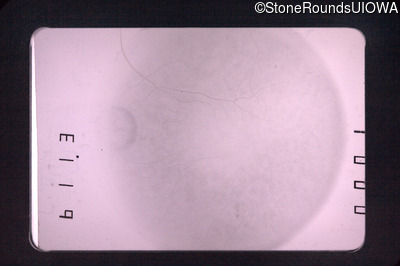

Fundus Montage - Right - 20/80 -1

Exemplar

Fundus Montage - Left - 20/200 -3